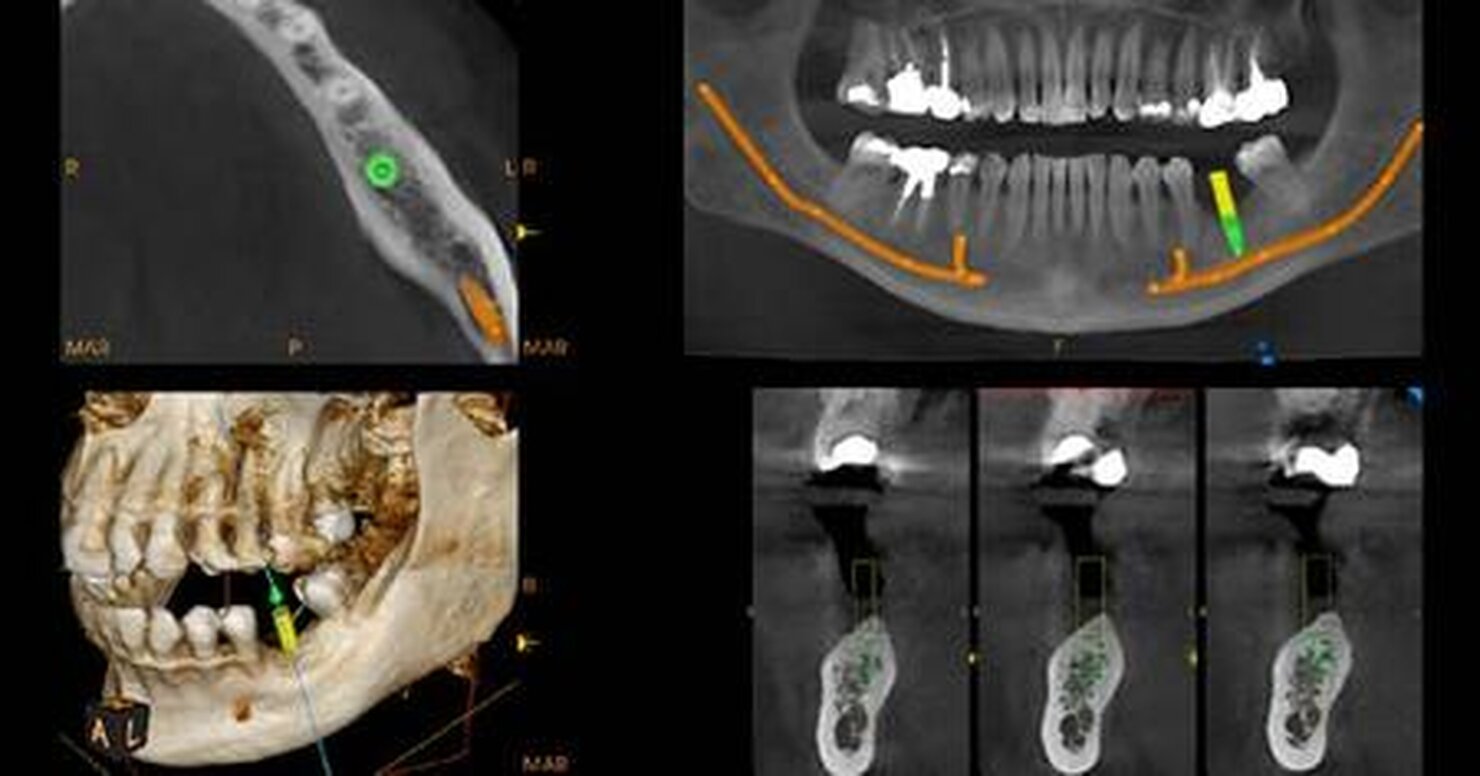

Sistema multifunzionale

Oltre all’imaging diagnostico, CS 8200 3D ti permette di ottenere modelli 3D digitali precisi che si integrano in modo rapido e lineare con applicazioni 3D opzionali, comprese quelle per pianificazione implantare e per ortodonzia.

Scansioni arcata

Le scansioni della arcata completa sono ideali per i casi che interessano l’intera dentatura.